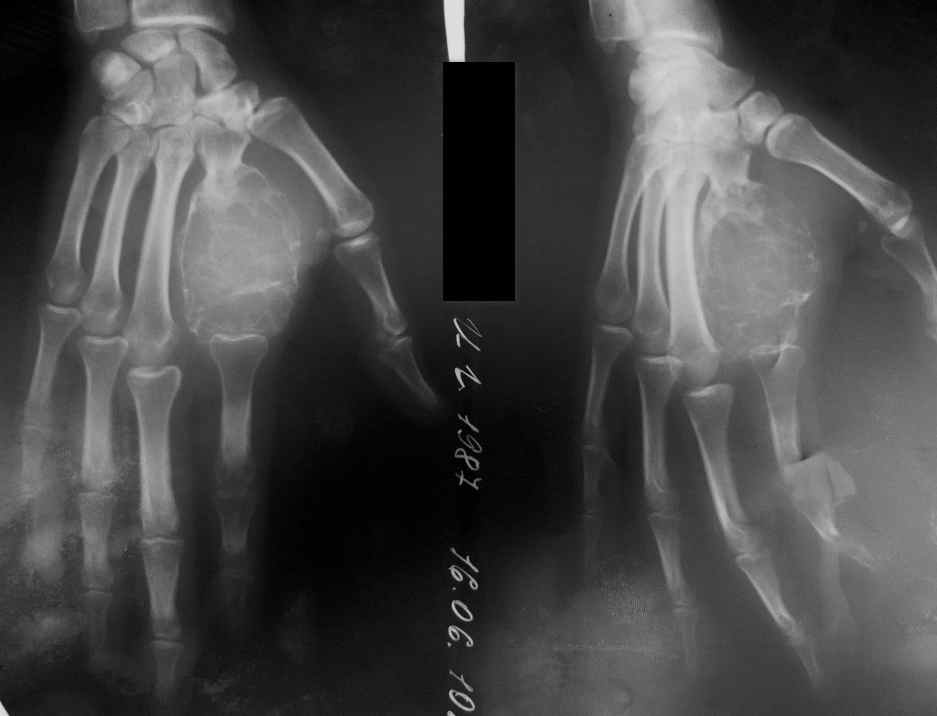

Уважаемый Максим, добрый вечер. А как вы планируете решить вопрос с суставной поверхностью пястной кости. Ведь судя по рентгенограмме 2-й луч уже потерял часть своей длины из за проседания пястной кости. Или вы ожидаете увидеть сохраненную хрящевую поверхность?

Я думаю, что конечно суставной поверхности там не осталось. Каковы будут предложения помимо артродеза пястно-фалангового сустава? Идти на неартроз?

На трехчетвертном снимке просматривается очертание головки пястной кости с суставной поверхностью. Поэтому какая-то надежда есть. И артродез, и ложный сустав - не очень хороший вариант для пястно-фалангового сустава трехчленного пальца. Но куда деваться? Хотя я мало верю в эффективность создания стабильного, подвижного, безболезненного ложного пястно-фалангового сустава.